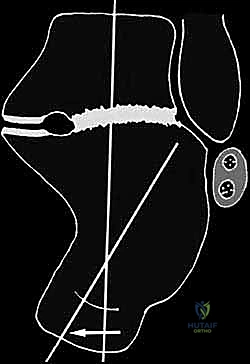

- القطع العظمي التصحيحي (Corrective Osteotomy):

إذا كان الكعب قد فقد ارتفاعه أو انحرف بشكل كبير، يقوم الدكتور هطيف بإجراء قطع دقيق في عظم الكعب لإعادة توجيهه إلى محوره الميكانيكي السليم. يتم استخدام طعوم عظمية (Bone Grafts)—تؤخذ غالباً من حوض المريض أو طعوم صناعية—لرفع الكعب المنهار واستعادة زاوية بوهلر الطبيعية.